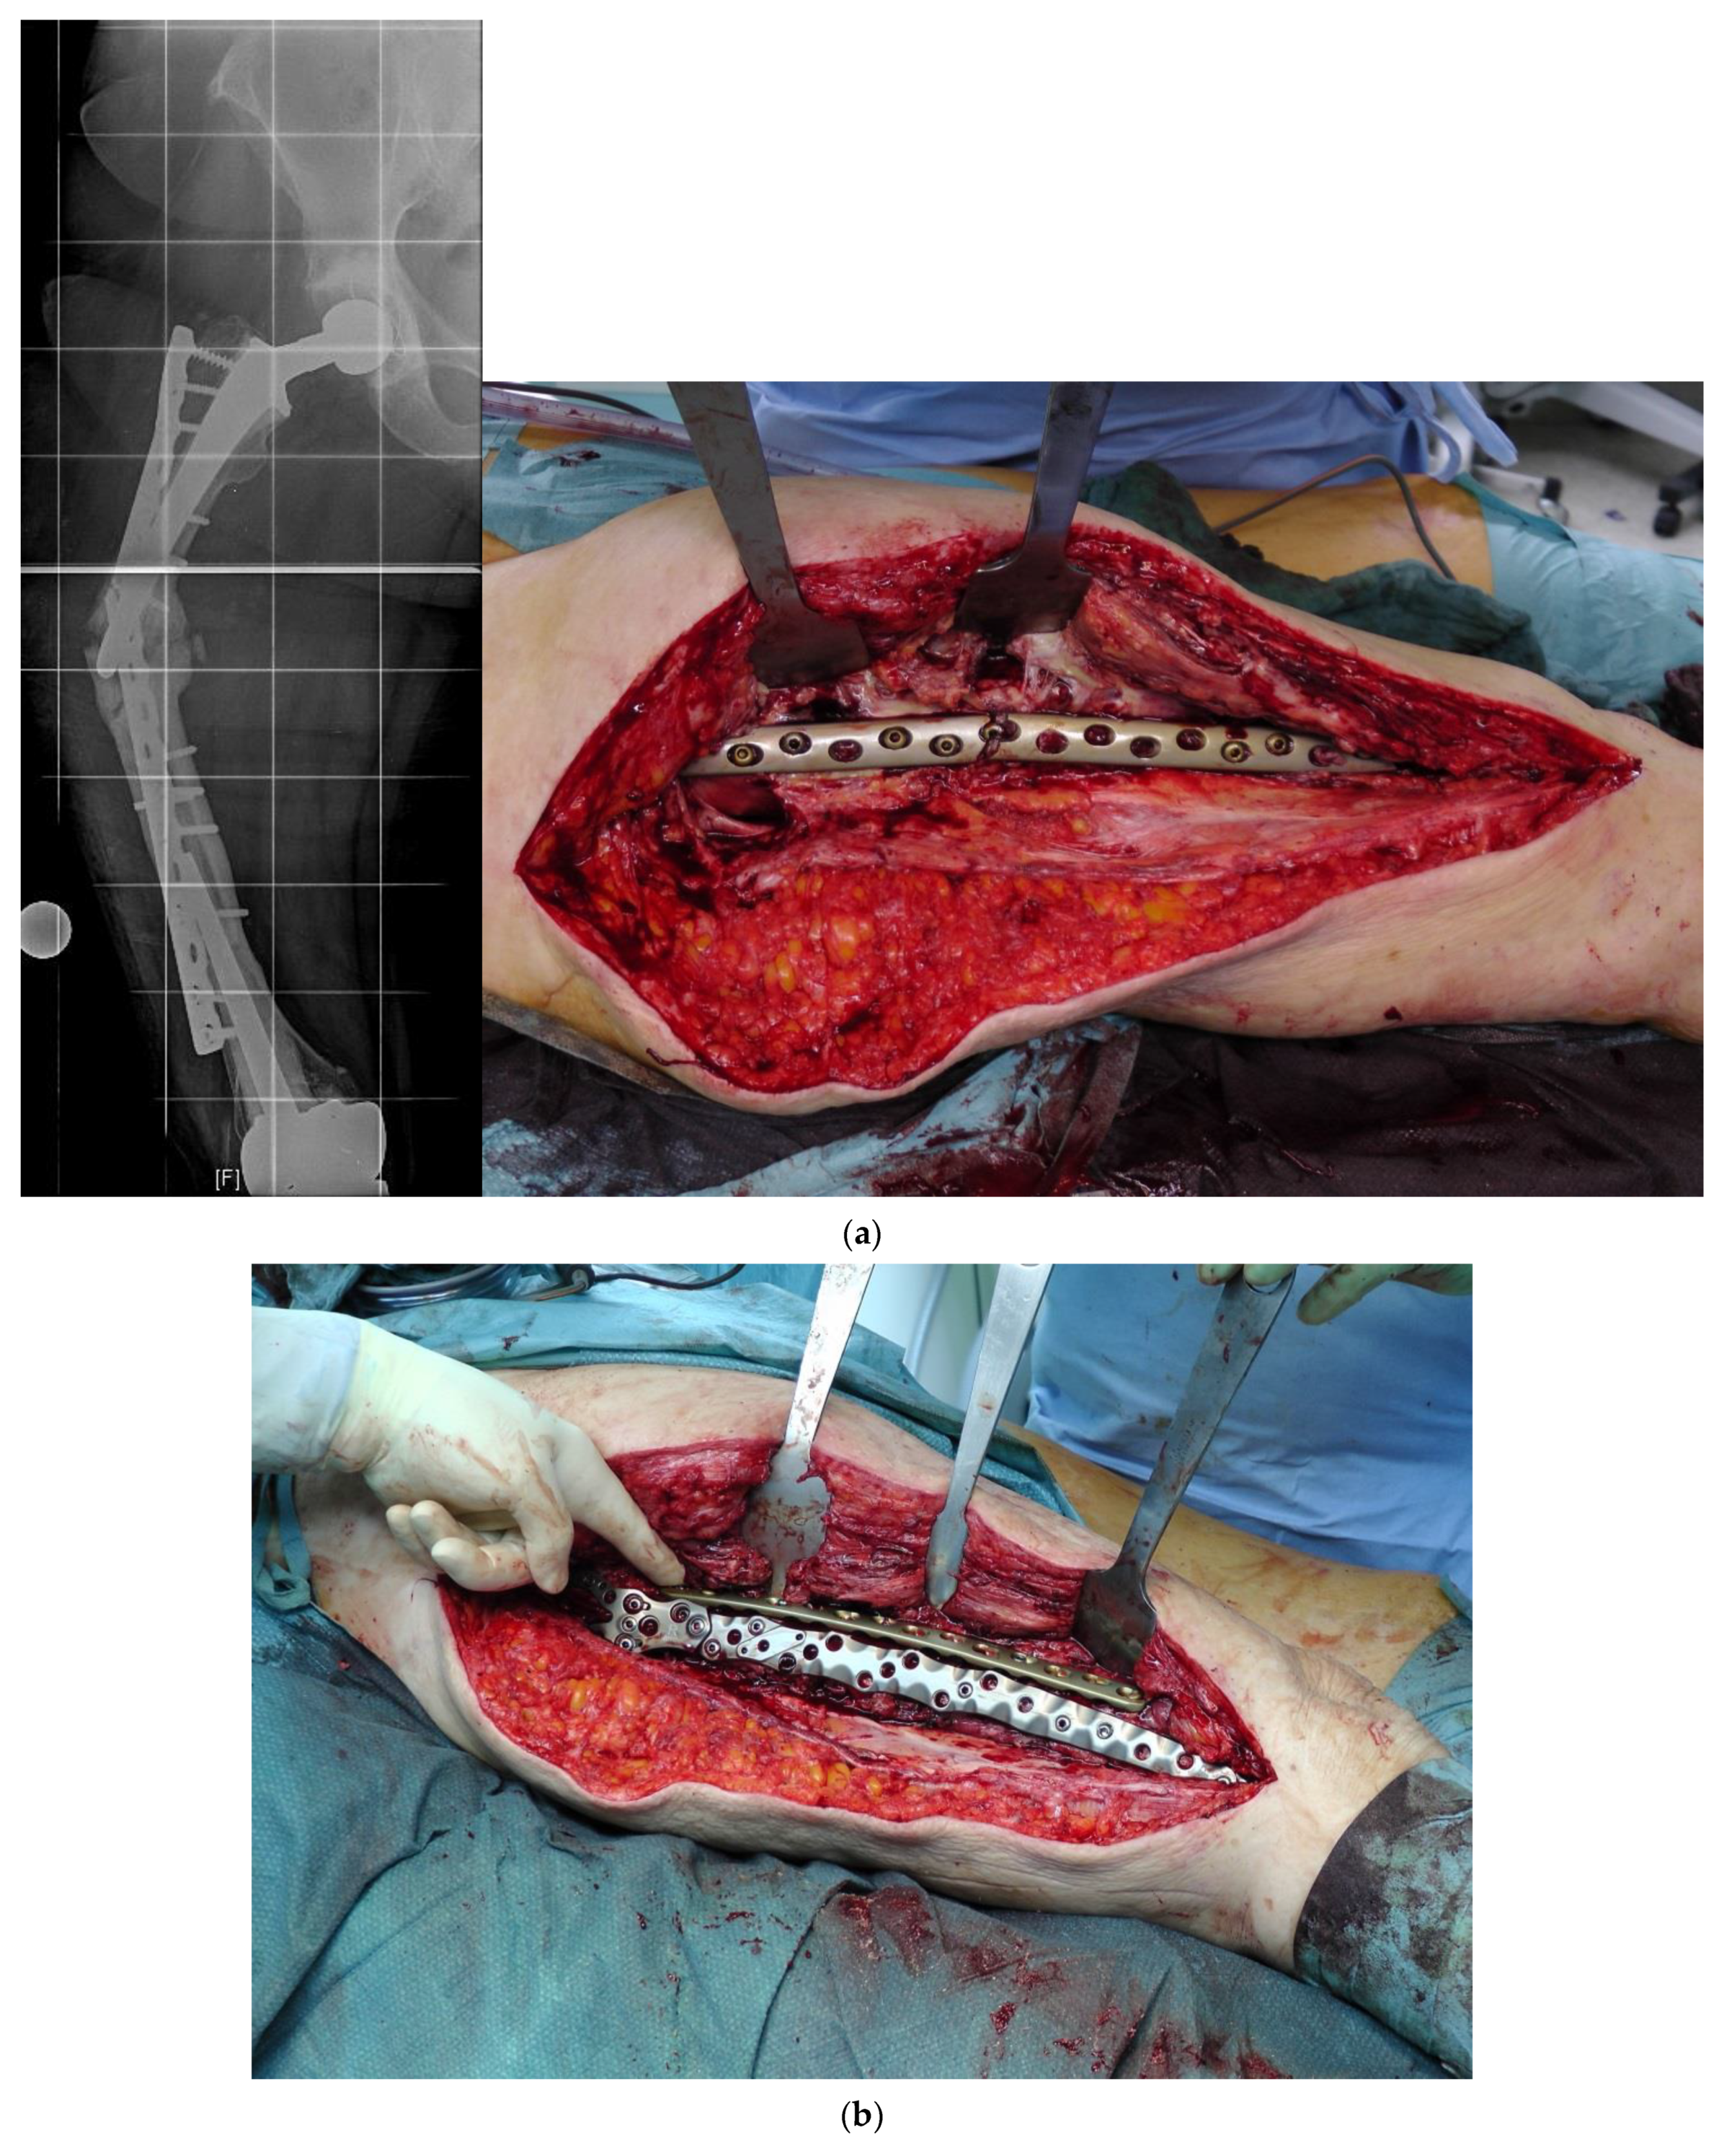

Although rare, interprosthetic fractures require cautious preoperative planning. Depending on the quality of the bone stock and the implant stability, either osteosynthesis via locked plates, the use of special devices such as docking tools (“Osteobridge®”, Merete Medical, Berlin, Germany) or custom-made interposition sleeves (AQ-Implants GmbH, Ahrensburg, Germany; “RescueSleeve®”, Waldemar Link GmbH, Hamburg, Germany) should be considered to avoid revision total hip replacement (RTHR) or a total femur implantation.

The “Osteobridge®” is a modular system which spans the fracture according to the distal and proximal end, respectively, over the implant stems of the endoprosthesis [29]. Interposition devices, such as the “RescueSleeve®”, are used to replace the fractured diaphyseal bone and to couple both ends of the hip and knee stem using two screws connecting the sleeves (Figure 5) [30], while custom-made sleeves could be used to couple a stable implant to a tumor endoprosthesis (AQ-Implants GmbH, Ahrensburg, Germany) (Figure 6).

Figure 6. Interprosthetic fracture around a stable total knee revision arthroplasty and a loose total hip revision arthroplasty. Implantation of a custom-made docking sleeve coupled to a proximal femur replacement (AQ-Implants GmbH, Ahrensburg, Germany).